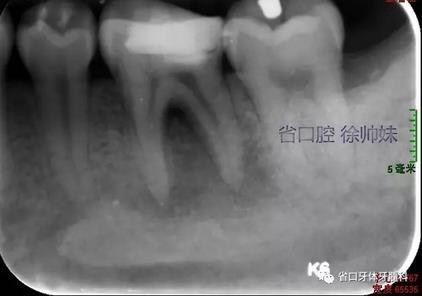

根尖片(圖2)示36大面積充填物近髓,根尖周及根分叉大面積低密度影。

圖2 術(shù)前根尖片